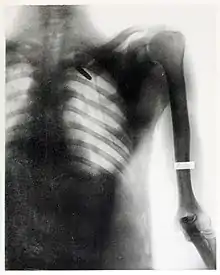

On August 20, 1899, she took one of her most famous radiographs, an image showing a Mauser 7 mm bullet lodged in the brain of John Gretzer Jr., in the region of the left occipital lobe.[12][15] Private Gretzer, of the 1st Nebraska Volunteers, wounded at Mariboa, Philippines on 27 March 1899 during the Spanish–American War. The private later returned to duty as a mail clerk.[16] Accounts of the case were reported in the 1902 edition of The International Text-Book of Surgery and in newspapers.[17] Another case of a bullet lodged in a soldier's skull, X-rayed by Fleischman was also reported in newspapers in 1899.[18]

She received praise for her work during the Spanish-American War from the Surgeon General of the Army George Miller Sternberg.[19] Several of her radiographs were also used by William C. Borden to illustrate his book on the medical use of X-rays in the Spanish-American War.[15]

She continued to work despite this injury.[20] In 1904, she was responsible for introducing protective measures for the operators of x-ray machines. She commented on the merits of double-plate glass screens, and metals such as lead, aluminium, iron and copper to "resist" x-rays.[22] By late 1904, the dermatitis progressed to cancer. Her doctors attempted to excise a tumor on her right hand, but this failed to halt the progression of the carcinoma. In January 1905 her entire right arm and scapula with the clavicle were amputated.[21] The 4 March 1905 edition of the journal Electrical World and Engineer published the details regarding the amputation of Fleishman's right arm and her withdrawal from the field of radiography and stated:[23]